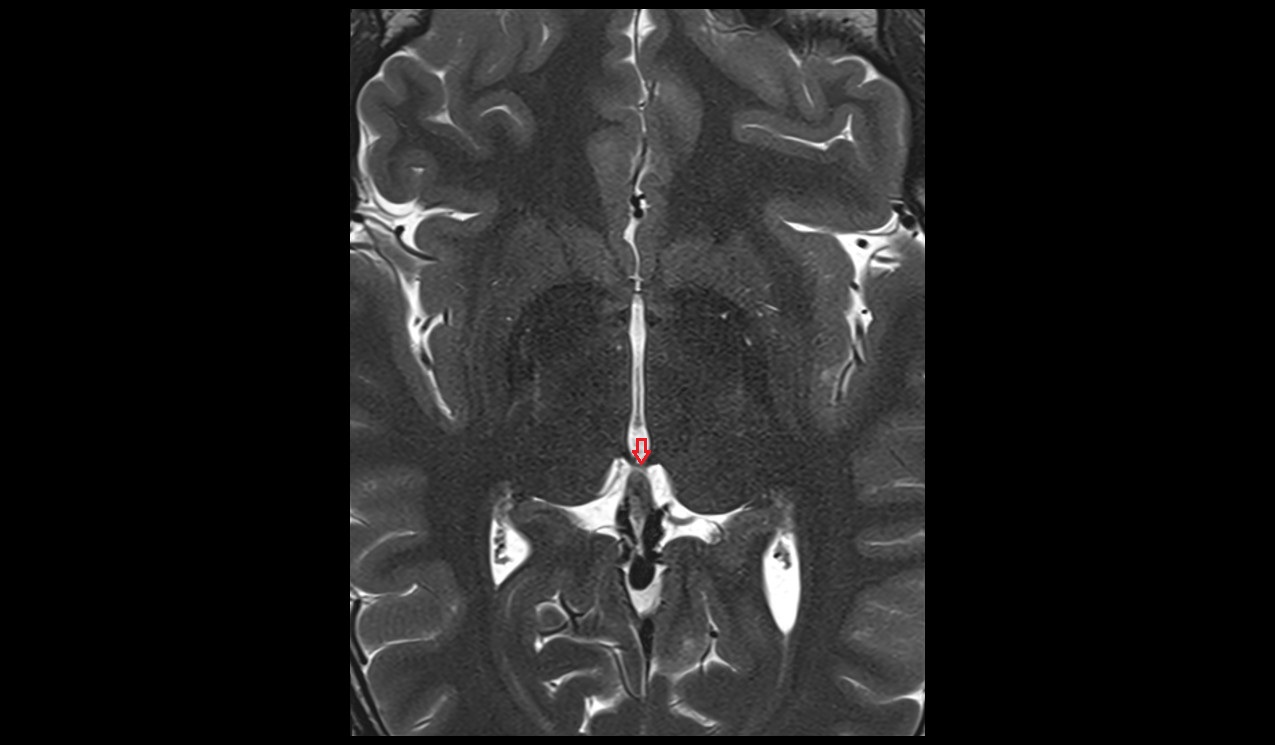

- Interthalamic adhesion

- Pituitary stalk

- Third ventricle